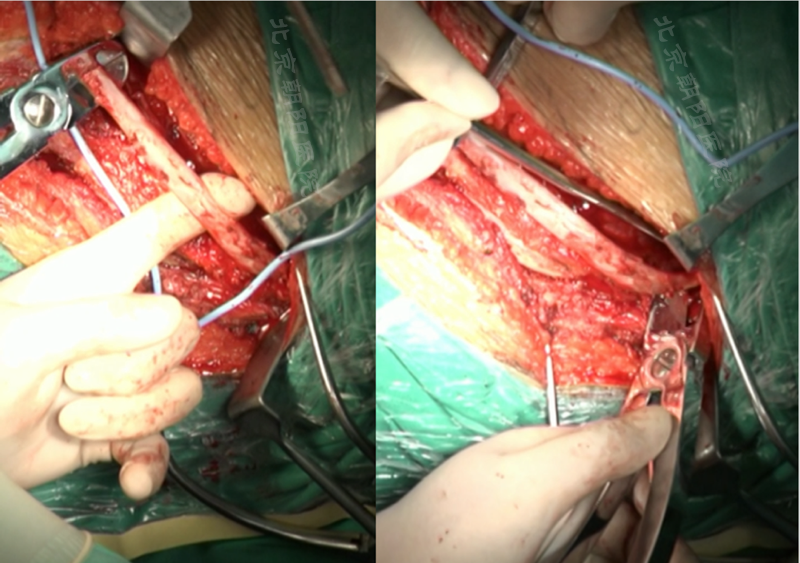

内固定选择的是5.5mm双棒系统,先置入顶椎的螺钉垫板。

置入顶椎的椎体螺钉,螺钉可置入椎体中部到后方1/3之间的范围内。

使用双棒系统时,先置入背侧的螺钉,螺钉指向椎体中线,后置入腹侧的螺钉,螺钉轻度指向后侧。形成对椎体的三角形抓持力。